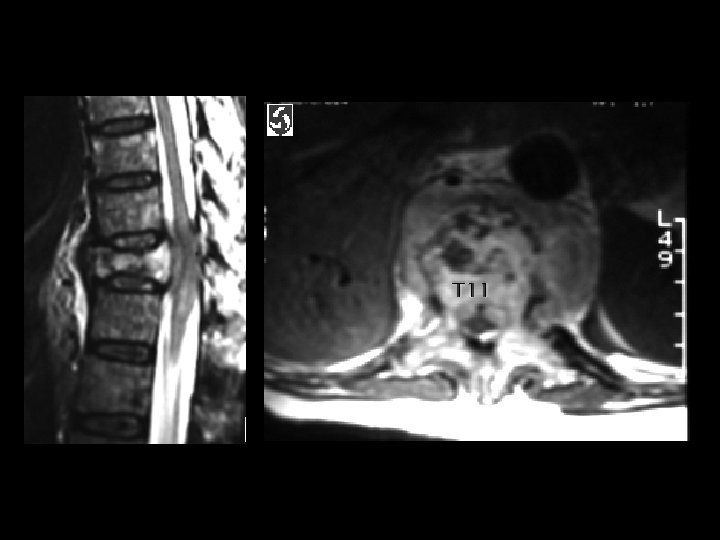

Pathologic compression fracture & cord compression • Findings: – Compression of T 11 with retropulsion and cord compression – Diffuse abnormal signal in the visualized vertebrae • Causes: – Metastases – Multiple myeloma